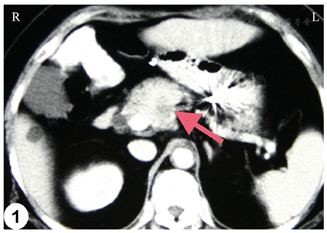

腹部超声提示胰颈前上方可见一3.6 cm×2.9 cm低回声肿块,边界不清,形态不规则;此外,提示胆总管轻度扩张以及胆囊多发结石。腹部强化CT提示胰腺颈部与胰头交界处可见不均匀强化团块,与肝总动脉关系密切(图1)。